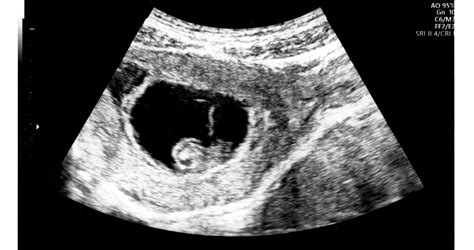

A leszívásra reggel, az előre megbeszélt időpontban kell menned, éhgyomorra. Előkészítenek téged az altatásra, majd következik a petesejtleszívás. A hüvelybe vezetnek egy ultrahangfejet, amire egy tű van erősítve (ez a punkciós tű) - ennek segítségével a hüvelyboltozaton keresztül a tüszőkben lévő tüszőfolyadékot leszívják.